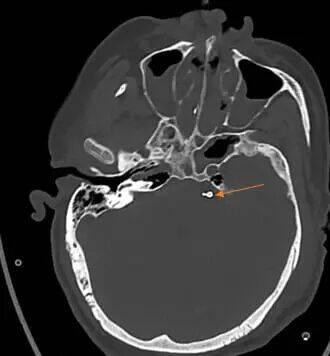

这一手术入路堪称神经外科手术的“高难度赛道”:手术区域深窄,视野暴露受限,术中操作空间极小,稍有不慎就可能损伤面听神经引发面瘫、听力障碍,或触碰脑干导致呼吸循环紊乱,手术风险极高。为确保手术万无一失,团队术前反复研读影像学资料(图1),并急诊先由主治医师张晓东、徐坤和耿仁强行脑血管造影(图2),依托神经介入指引精准标记出动脉瘤的位置、大小及与周边组织的毗邻关系;争分夺秒完善相关准备工作后行开颅动脉瘤夹闭术,术中在高倍手术显微镜下,以毫米级精度仔细分离蛛网膜粘连,小心避开神经血管“禁区”,精准选择适配的动脉瘤夹,成功将动脉瘤颈完全夹闭(图3术中动脉瘤夹位置)。术后复查头颅CT(图4)显示,动脉瘤夹位置精准,动脉瘤无残留显影,周围血管神经未受任何损伤。

术后头颅CT复查影像显示,动脉瘤夹位置良好,动脉瘤无显影。